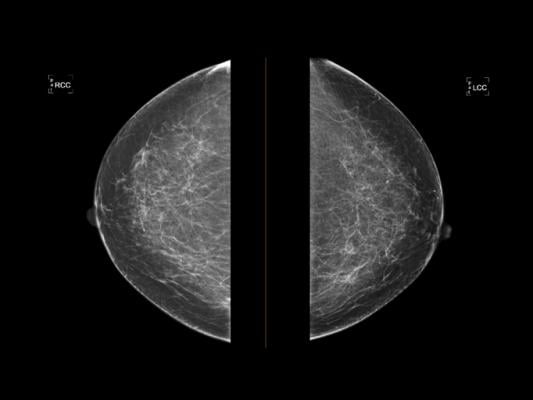

December 29, 2020 — The American College of Radiology (ACR), Society of Breast Imaging (SBI), patient advocates and others secured an extension of the moratorium on harmful 2009 and 2016 United States Preventive Services Task Force (USPSTF) Breast Cancer Screening Guidelines from Dec. 31, 2021 to Dec. 31, 2022. Without this added protection gained in the Consolidated Appropriations Act, 2021 (Omnibus and Coronavirus Relief Bill), under the Affordable Care Act (ACA), mammography coverage for women younger than 50 may have been impacted starting Jan. 1, 2022. The newly passed bill ensures that women ages 40 and older who want annual screening mammograms will retain insurance coverage with no copay.

The new legislation continues to recognize 2002 USPSTF guidelines for coverage decisions. The 2002 guidelines call for screening every one to two years starting at age 40 — rather than delayed and less frequent screening allowed under 2009/2016 USPSTF recommendations.

The Affordable Care Act (ACA) requires insurers to financially cover exams given a grade of “B” or higher by the USPSTF (with no patient cost sharing). The USPSTF assigned routine screening of women ages 40–49 a “C” and gave a “B” grade only to every other year screening of women 50–74. Women 40–49 who want routine screening and those 50–74 who want annual rather than biennial screening would not have been guaranteed coverage after Jan. 1, 2022 without the moratorium extension.

Published analysis, using the task force’s 2009 methodology, showed that, if the 2009/2016 guidelines were used, approximately 6,500 additional women in the United States would die from breast cancer each year. Many more would experience more extensive and expensive treatments than if their cancers were identified earlier by routine mammography.